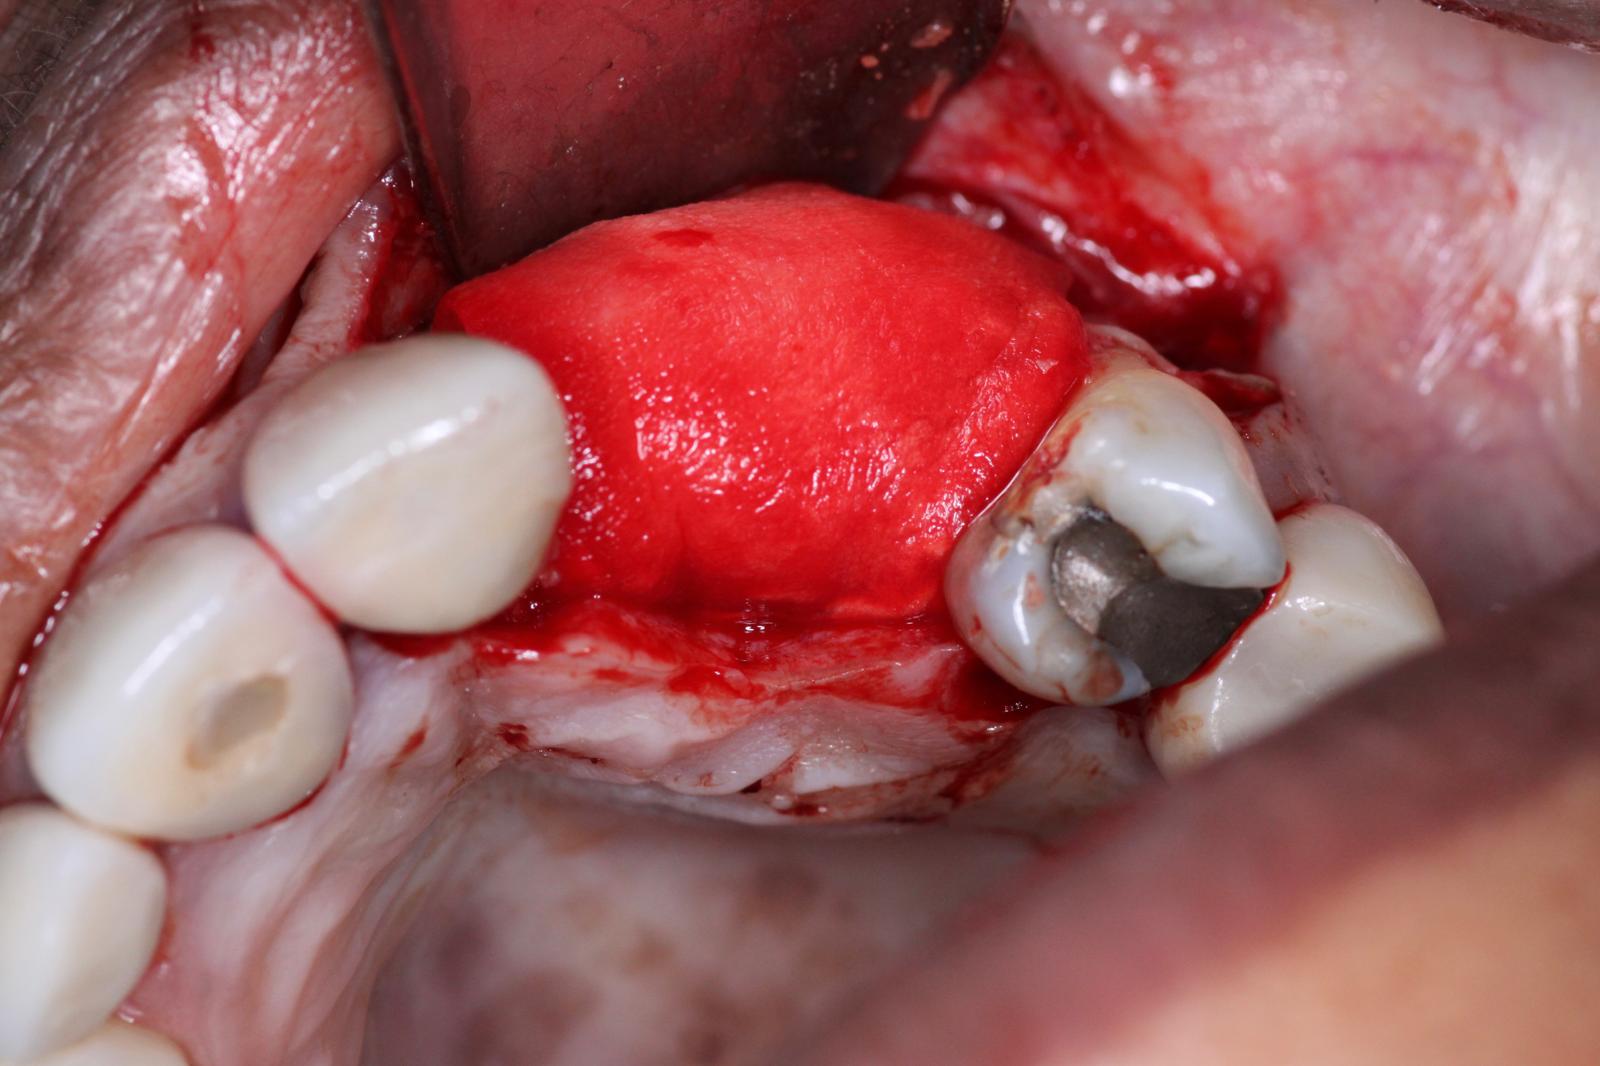

Finally, we sutured the site using Chromic Gut sutures. It is critical in GBR to get primary closure. In this particular case because of how much bone volume we are adding, a very deep periosteal release was done we we could pull over all the tissue from the buccal and suture the site as passively as possible. For more information this suturing technique, please see: Bone Regeneration of Extensive Socket Defects with Immediate Implant Placement